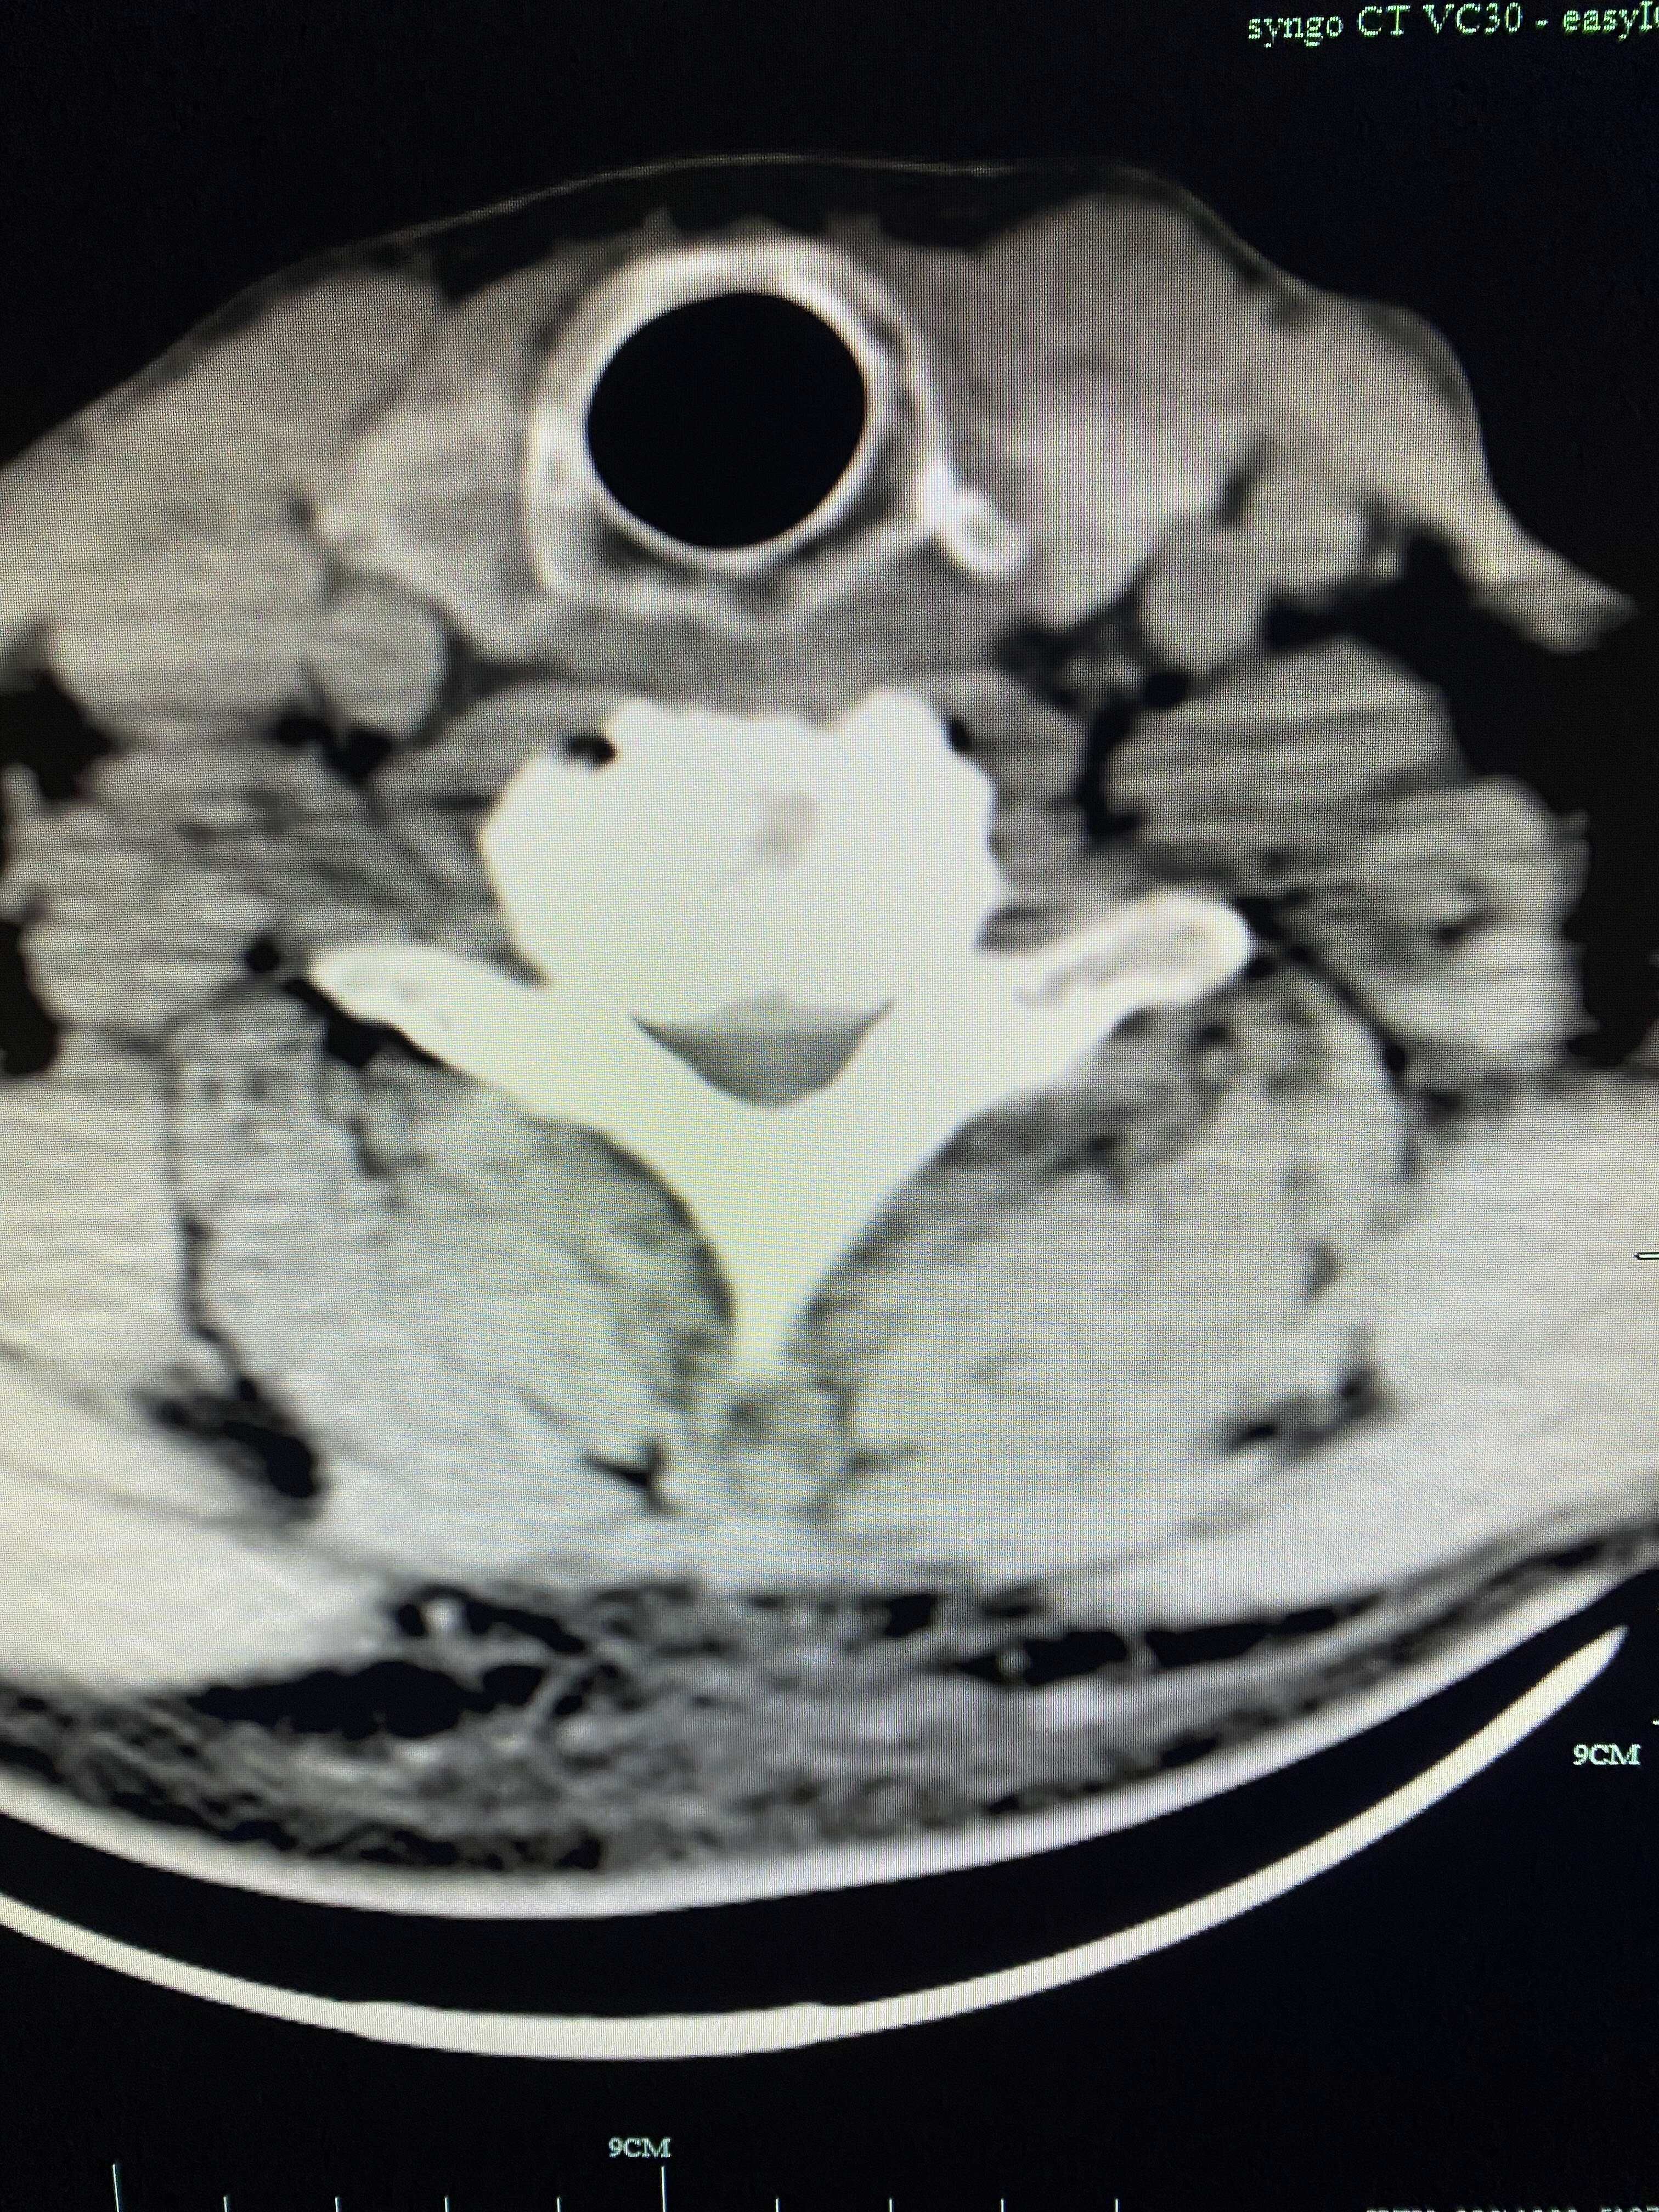

颈椎CT轴位片示:间盘突出钙化、颈椎管狭窄